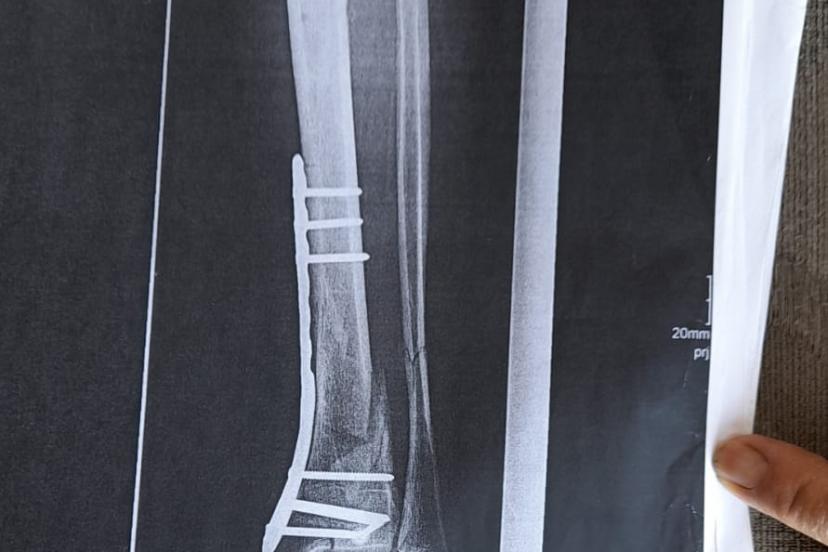

Olay yeriyle ilgili fotoğraf ve görüntüleri mahkemeye sunduklarını kaydeden Güray, "Ömrümü yediler, demir var ayağımda, sakat bıraktılar. Ayağı keseceklerdi neredeyse. Şu an kalıcı sakatlık var. 1 sene kendime gelemedim, 2 haftada bir ameliyata giriyordum. Almanya'da 3 ay hastanede kaldım ve ayağımda yüzde 3'lük engel oluştu" diye konuştu.

Tazminat miktarını düşük bulan Yunus Güray, şunları söyledi: "Benim uçak masrafım sadece 22 bin avro tuttu. 9 yıl oldu, bir tane çukur değildi. Adamlar kazmış, kazmış, bırakmış. Tam merkezde bu olay, hani ormanda bir yerde olur, 'Tamam benim de hatam var. Gittim de düştüm' derim. Ama şehrin merkezinde, etrafı çevrili değildi. Yemyeşil alan, gece vaktiydi. Ben mahkemeye verdim, o çukurları 3 ay sonra kapattılar. 6- 7 yerde kazılmış çukurlar vardı. Bir tane değildi. Ayağımda hala demir var. Adil bir karar olmadı."